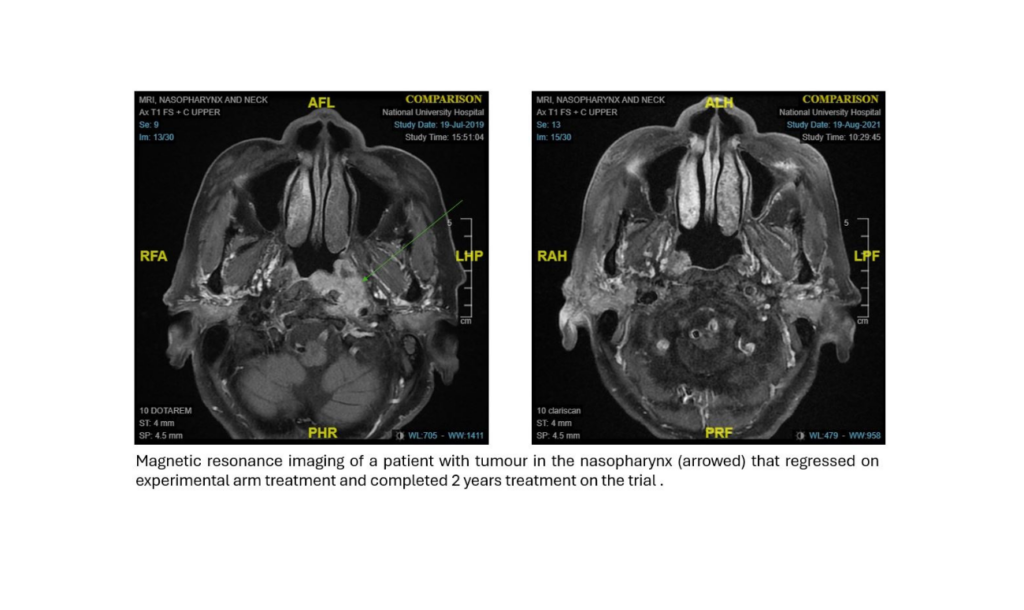

Efficacy of Combined Pembrolizumab and Bevacizumab in Platinum-Resistant Nasopharyngeal Carcinoma

Nasopharyngeal carcinoma (NPC) is common in South China and parts of Southeast Asia. Despite treatment, 20-30% of patients relapse within five years and ultimately become resistant to standard platinum-based chemotherapy; […]